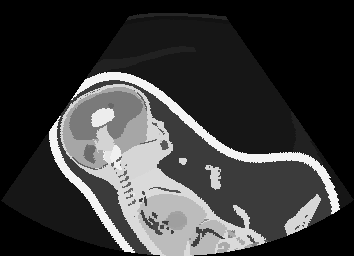

In Fig. 3 we show that only learning an auxiliary seg-to-real translation, i.e. CUT+S, cannot guide the network to learn the semantics of simulated images.

CUT+SC with the loss term largely reduces hallucinated image content, although it still fails to generate fine anatomical details. With the multi-domain conditional generator and additional losses of ConPres, translated images preserve content and feature a realistic appearance. Training without leads to training instability.

Comparison to state-of-the-art. As seen qualitatively from the examples in Fig. 3, our method substantially outperforms the alternatives in terms of content preservation, while translating realistic US appearance. CycleGAN, SASAN, and CUT hallucinate inexistent tissue regions fail to generate fine anatomical structures, e.g. the ribs. StarGAN fails to generate faithful ultrasound speckle appearance, which leads to highly unrealistic images. Our method ConPres preserves anatomical structures, while enhancing the images with a realistic appearance. It further faithfully preserves acoustic shadows, even without explicit enforcement. However, as seen from the last column, the refraction artefact appears artificial in the images translated by all the methods. Note that although the imaging field-of-view (FoV) and probe opening in the simulation is significantly different from the real in-vivo images (Fig. 2) used for training, our ConPres maintains the input FoV closely compared to previous state-of-the-art. The results in Tab 2 quantitatively confirm the superiority of our method. Note that SSIM and FID/KID are used to measure translation performance from two different and sometimes competing aspects, with the former metric for quantifying structure preservation and the latter metrics for image realism.